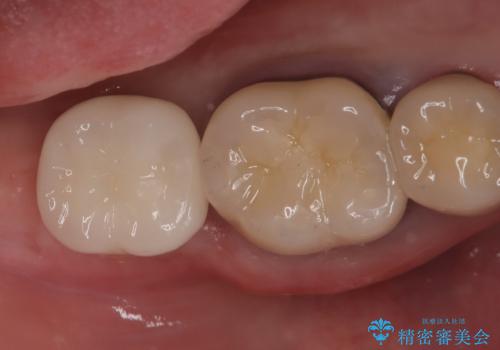

- 「他院で治療した被せ物が外れた」を主訴に来院された患者様です。診査診断を行い歯の保存が困難だったため抜歯後、インプラントで治療しました。

インプラントを入れるためには十分な骨の高さと幅が必要です。術前に検査を行い必要であれば別途、骨や角化歯肉を増やす治療も行う事があります。

インプラントの土台と被せ物は適合が良い物を制作するため、シリコン印象材を使用し型を取っています。